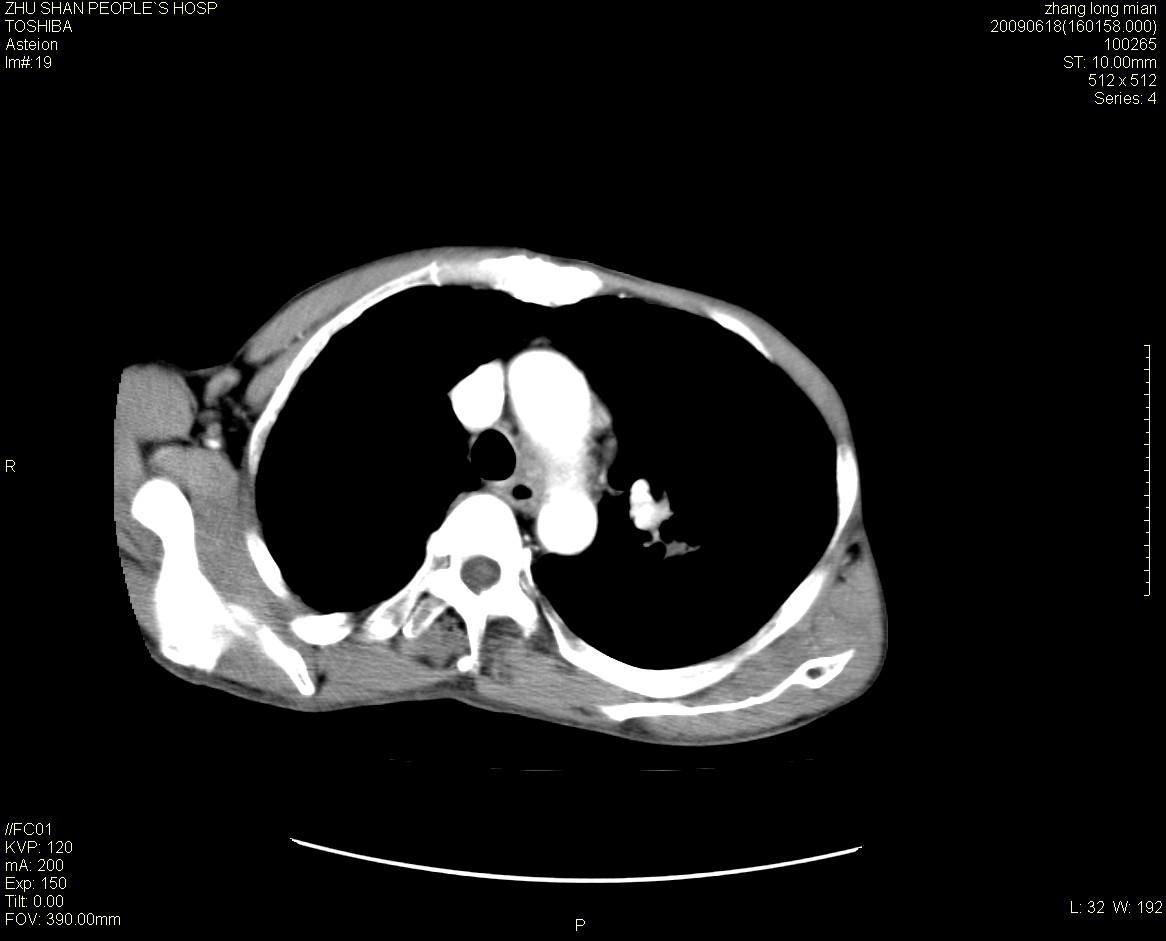

男性 65岁 胸片发现右下肺包块.诊断肺ca并纵隔转移没有问题吧!

两侧胸廓不对称,右侧呈塌陷改变,右肺萎缩。

右下肺见浅分叶状软组织块影,边缘有毛刺,其下部似见不完整偏心空洞影,邻近胸膜凹陷征,并胸腔积液。

增强见纵隔区气管隆突上下及左肺门区肿大淋巴结。左肺感染性病灶。

另见右上肺见一枚小结节影,性质待定。